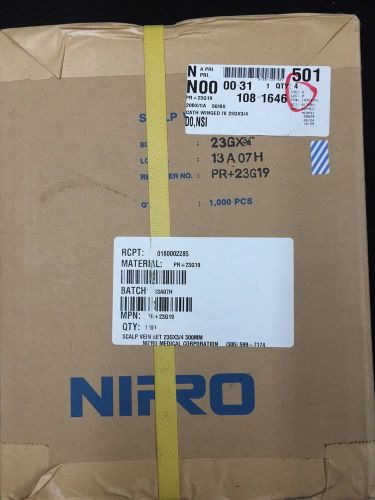

Cath Winged IV 23Gx3/4 50/BX 20Bx/CS - Nipro Part #PR+23G19